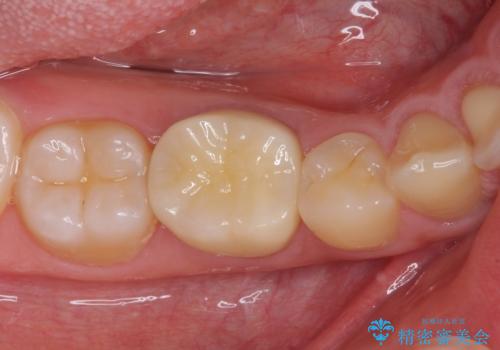

虫歯除去後に痛みは収まり、神経も保存することができました。

変色していた歯もセラミッククラウンで自然な色合いとなり、患者様には大変満足していただきました。